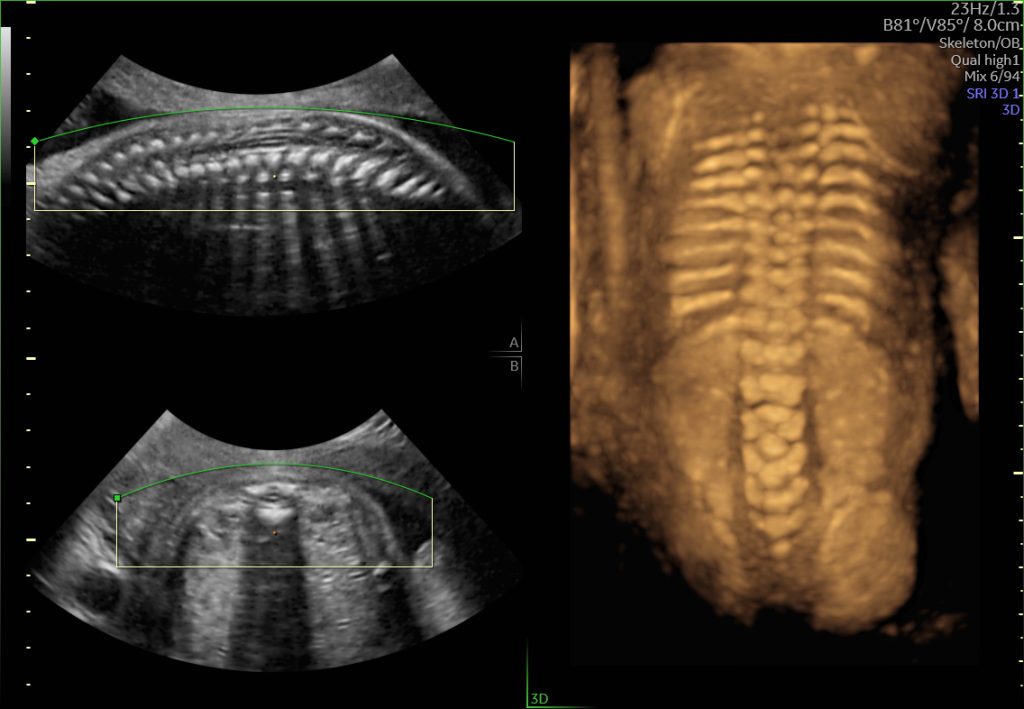

3D ultrasound is a still image of the baby. 4D ultrasound displays moving image of the baby. HD live with — latest scanning machine (voluson switch). Those offer a period of view of you baby very close to viewing a live baby.

Our 3D scans enable you to see your growing baby before that all- important day. Keep the moment treasured forever with our detailed 3D colour photos and capture your baby’s movements on DVD. Peep into your baby’s magical world on this video. Our 4D scan enables you to see your growing baby before that all- important day. Keep the moment treasured forever with our detailed 3D colour photos and capture your baby’s movements on DVD.